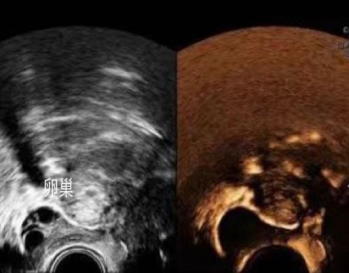

是在宫腔内放入子宫造影管,然后推入造影剂,造影剂会沿着双侧的输卵管流入盆腔,通过超声显象动态观察输卵管是否通畅,输卵管的走形、子宫形态以及宫内的占位、病变等情况。